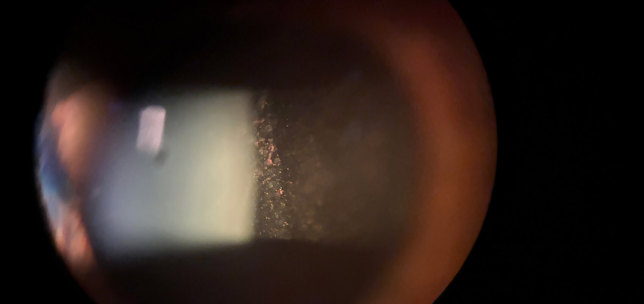

The ANTerior Segment Imaging Competition from Eye News and Keeler promotes and celebrates the work of slit-lamp imaging, culminating in cash prizes and exposure for its winners.

After a successful run in 2024, the ANTS Imaging Competition returned this year with another overwhelming response and our judges were thrilled to have so many amazing images to choose from. We would like to offer a huge congratulations to our winners, honorary mentions, and shortlisted entries, all of which can be seen below. So, without further ado, here some of the best ophthalmic imagers, optometrists and allied professionals in the UK right now: